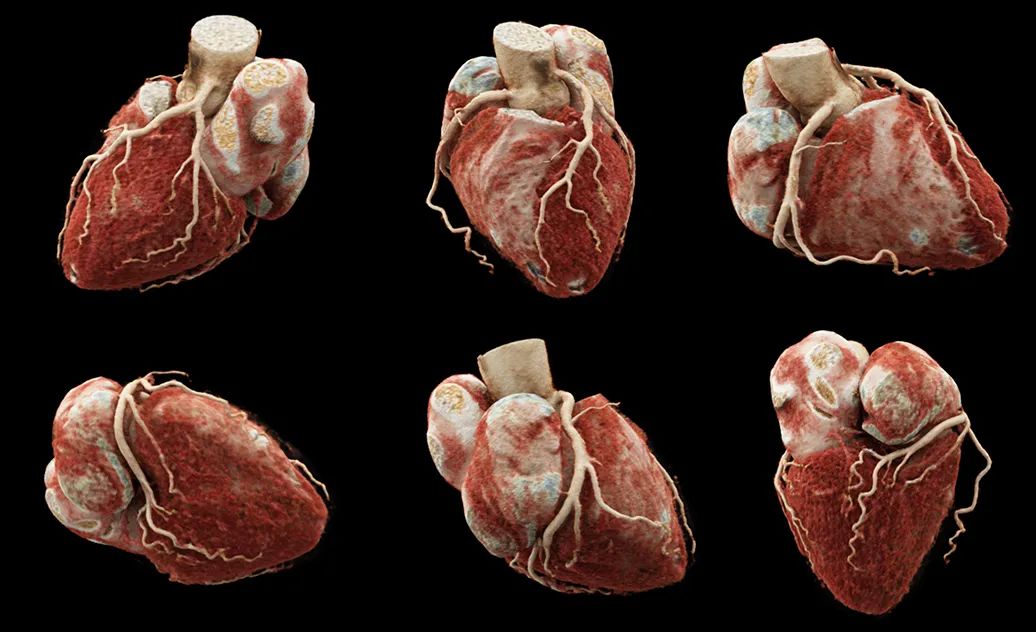

2、全息仿真VRT

生動(dòng)形象地展示心臟和血管的立體圖像

心臟

左、右冠狀動(dòng)脈